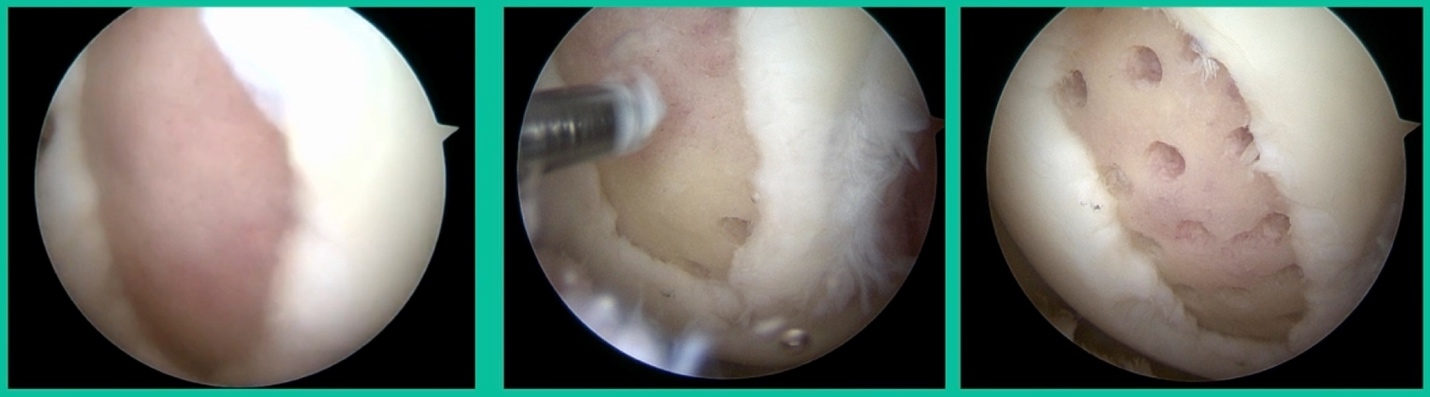

We get in there, it’s delaminated, not much bone, nothing to fix in my mind, and so we drilled it.

How do these do? There’s actually reasonable data for marrow stimulation for OCD. But if you have the option for small defects, I would prefer an osteochondral allograft over microfracture based on the literature. That’s the take-home. Marrow stimulation, if you do it, you’re probably better off drilling it. We showed that we could reduce revision rates with marrow stimulation by two-thirds if you drill it versus use a microfracture awl.